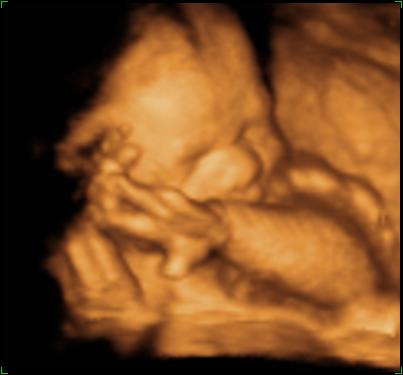

27 Week 3D/4D Scan on 04 May 2006